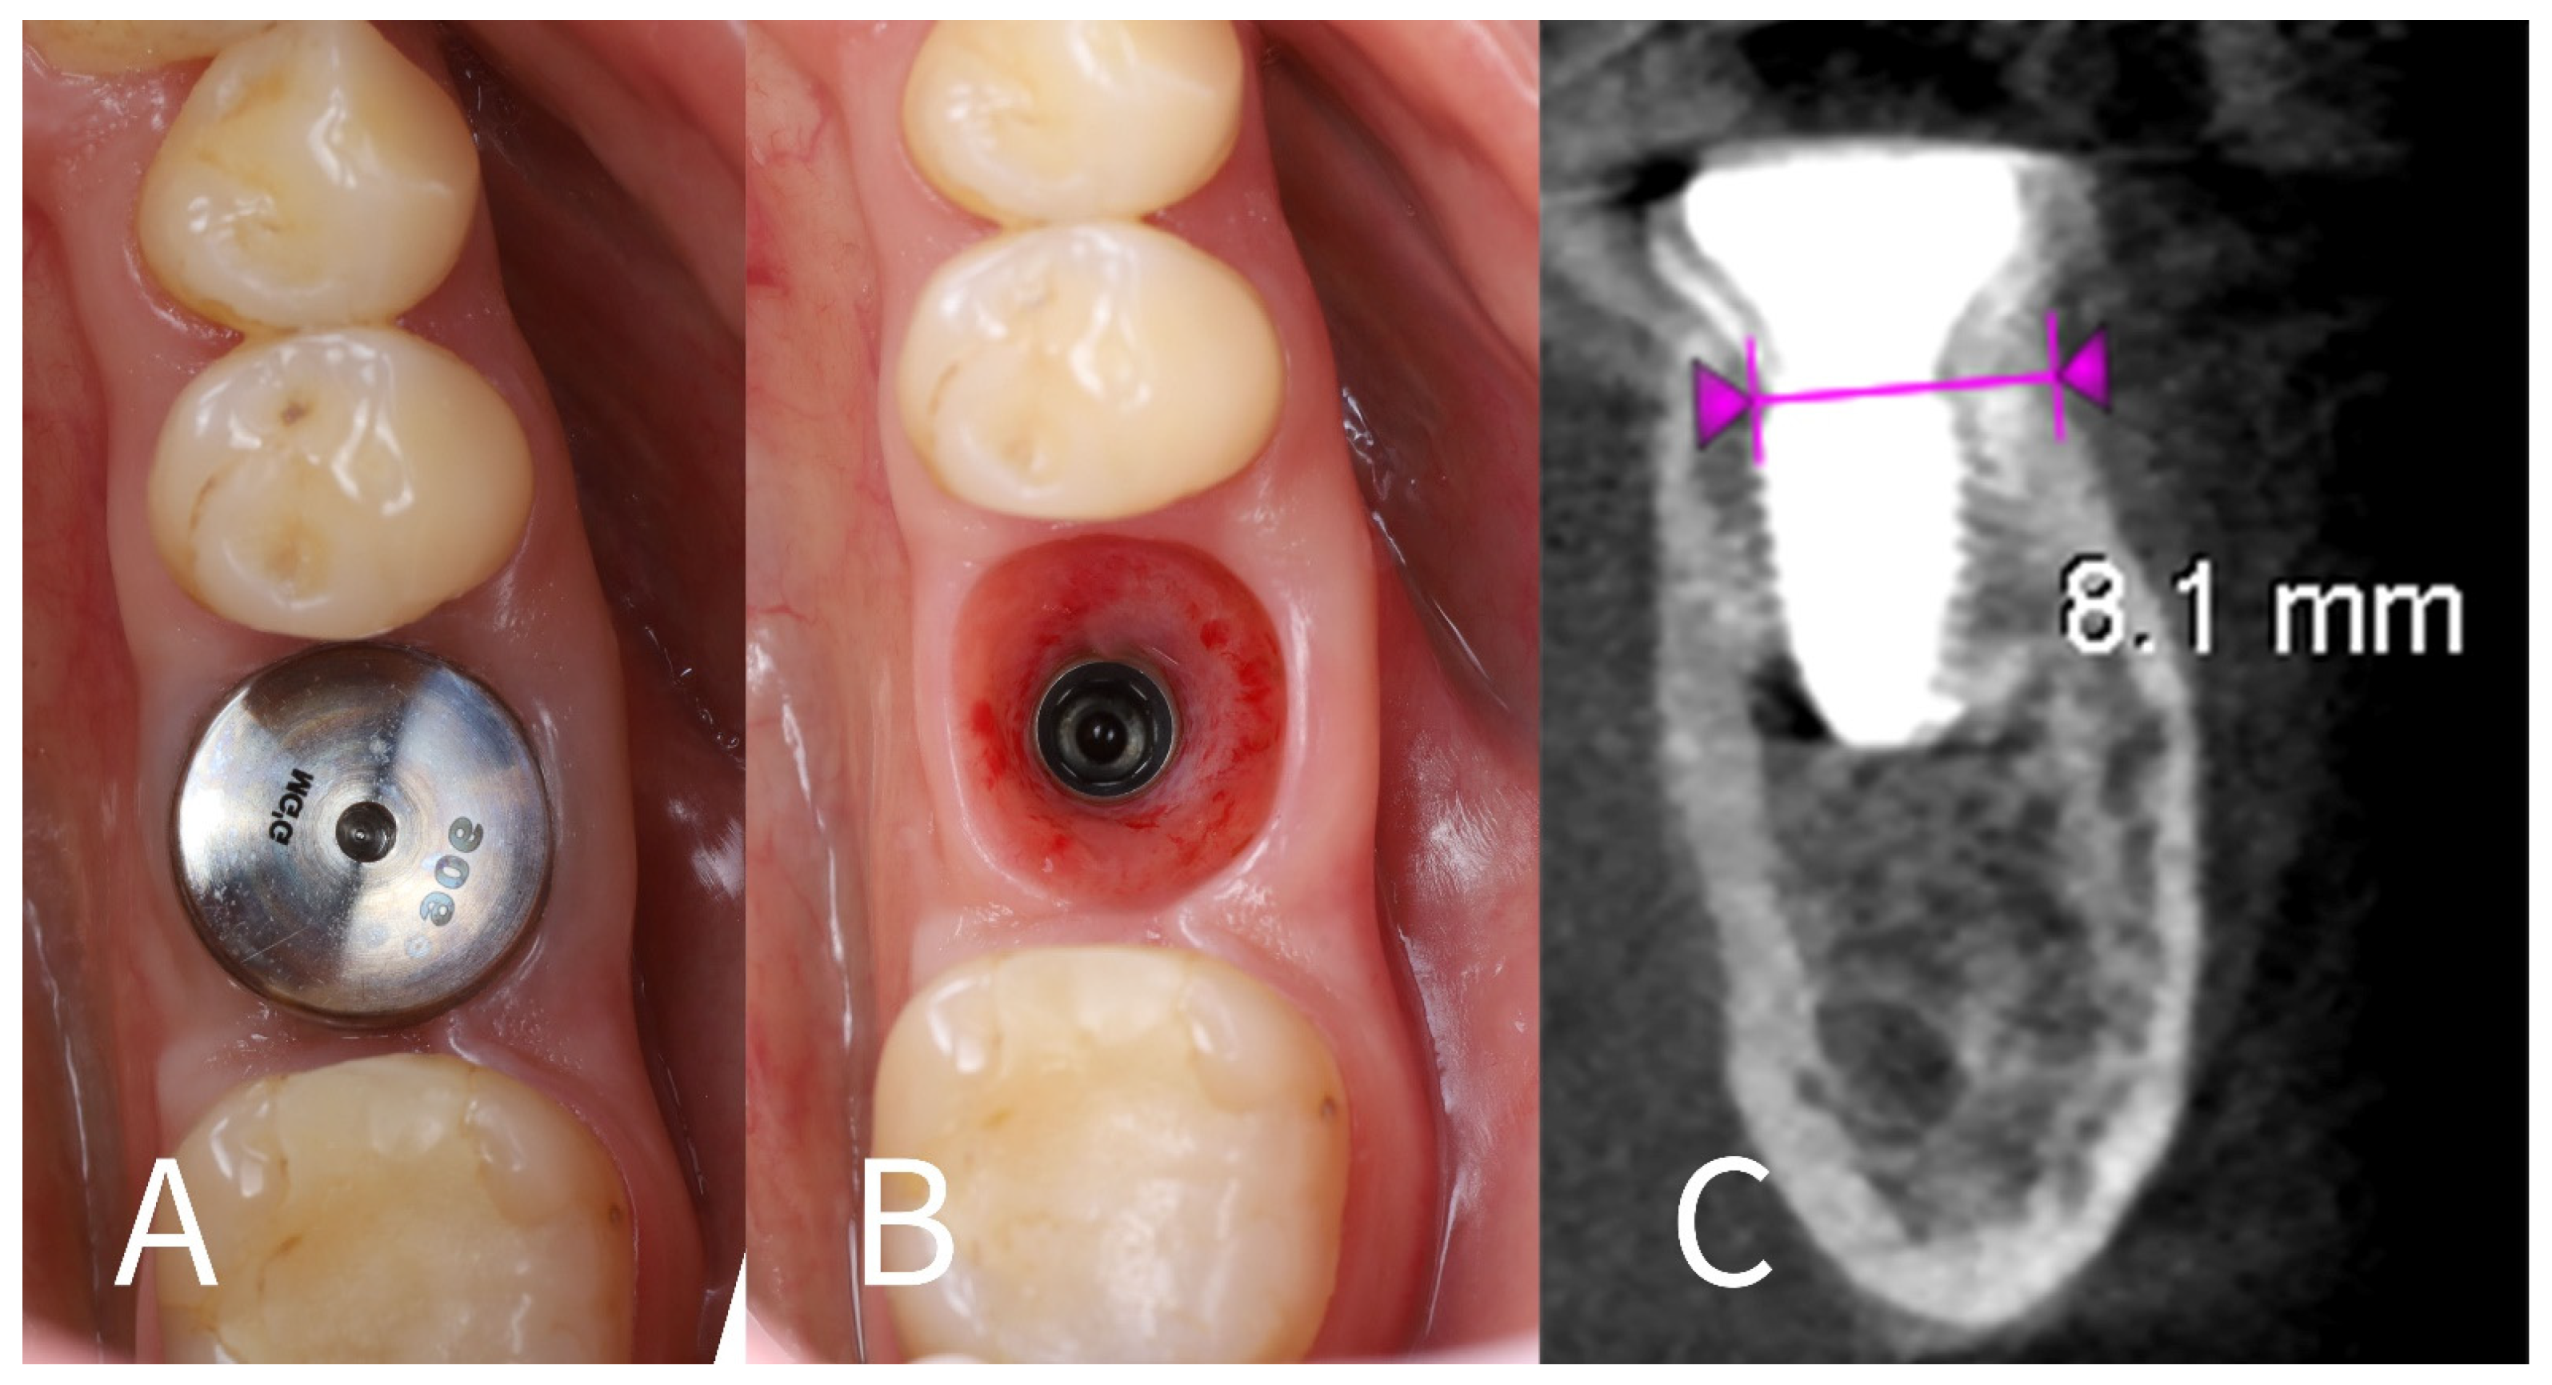

- Socket sealing with healing cap: The socket orifice was sealed with a large-diameter healing abutment instead of suturing a flap. A wide, 9 mm diameter, and 6 mm height standard healing cap was attached to the implant, which effectively covered the socket opening and conformed to the circumference of the socket (Figure 5). This approach is intended to protect the socket and support the surrounding gingival margins without requiring a flapped closure or graft. No additional bone graft or membrane was placed in the socket; a blood clot was allowed to fill the gaps between the implant and shields [17].

- Immediate post-op imaging: A postoperative CBCT scan was obtained to evaluate the implant position and to measure the alveolar ridge dimensions after implant placement (Figure 6). CBCT confirmed that the implant was accurately centered in the socket.